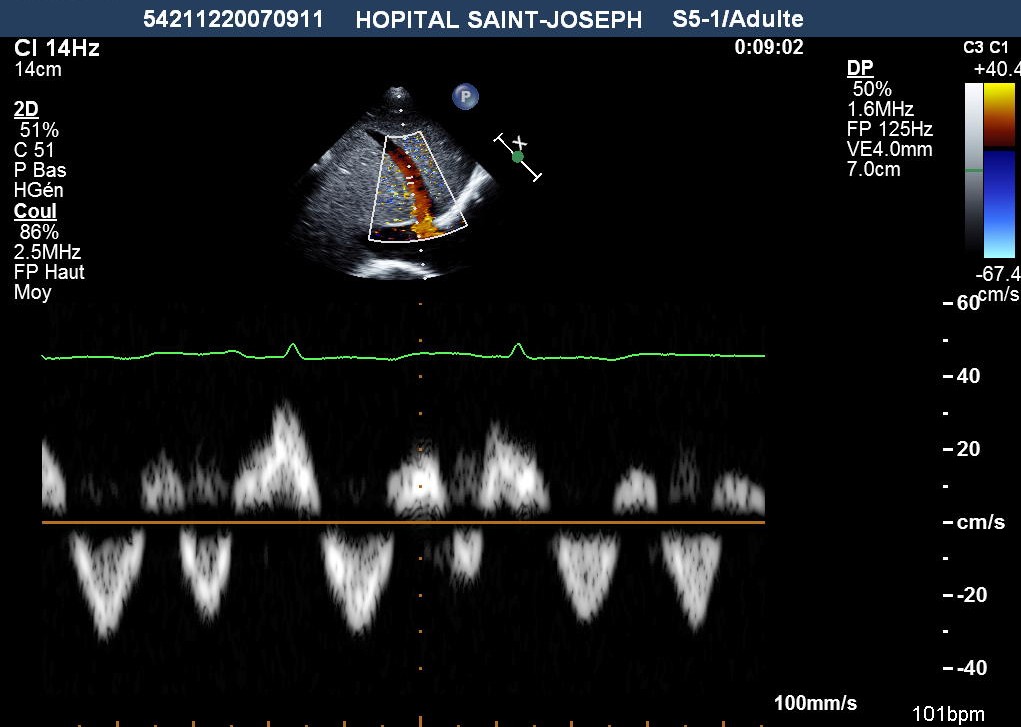

Flux Doppler dans les VSH avec une aspect en W chez ce patient avec la PCC tuberculeuse: